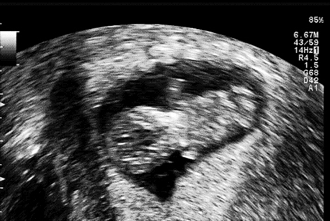

Crash ohne Folgen! - Tagebücher aus der Schwangerschaft von Ophelia aus Köln

Eine neue wunderbare, aufregende und vielleicht auch lang erwartete Lebenszeit beginnt. Für unsere Tagebücher-Blogs haben wir immer 3-4 schwangere Frauen in unterschiedlicher Schwangerschaftsphase, die in freudiger Erwartung über jede Woche dieser spannenden Zeit schreiben, uns und die vielen tausend Follower:innen daran teilhaben lassen und damit unvergessliche Momente schaffen.